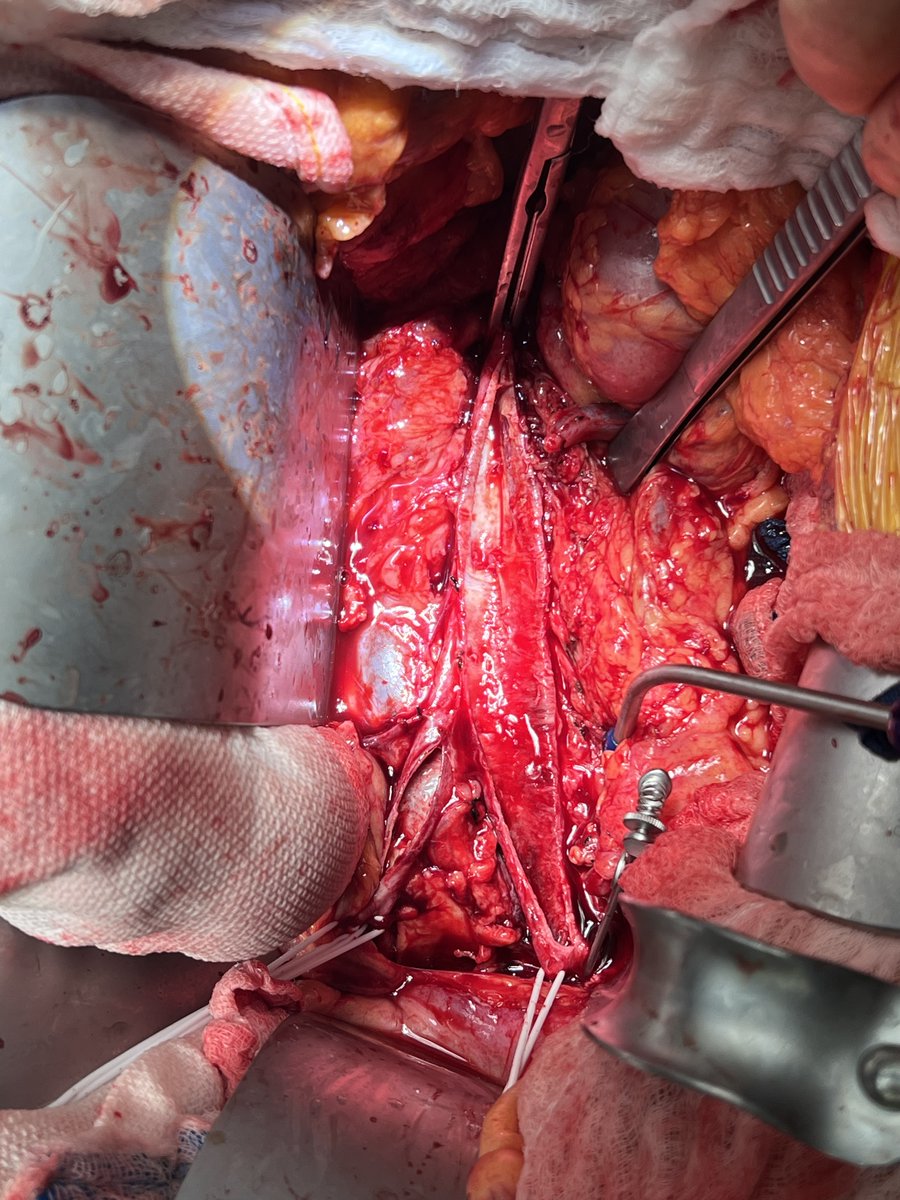

This organ is going to be replaced. Retroperitoneal exposure. First branch superiorly, the left renal artery. The IMA has been clipped and divided. Good exposure through small flank incision. #AortaEd